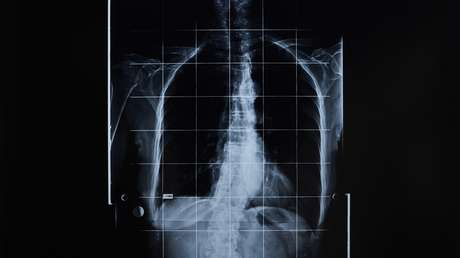

Científicos de todo el mundo unifican criterios para determinar el diagnóstico de muerte cerebral 16 ago 2020, 09:54 GMT